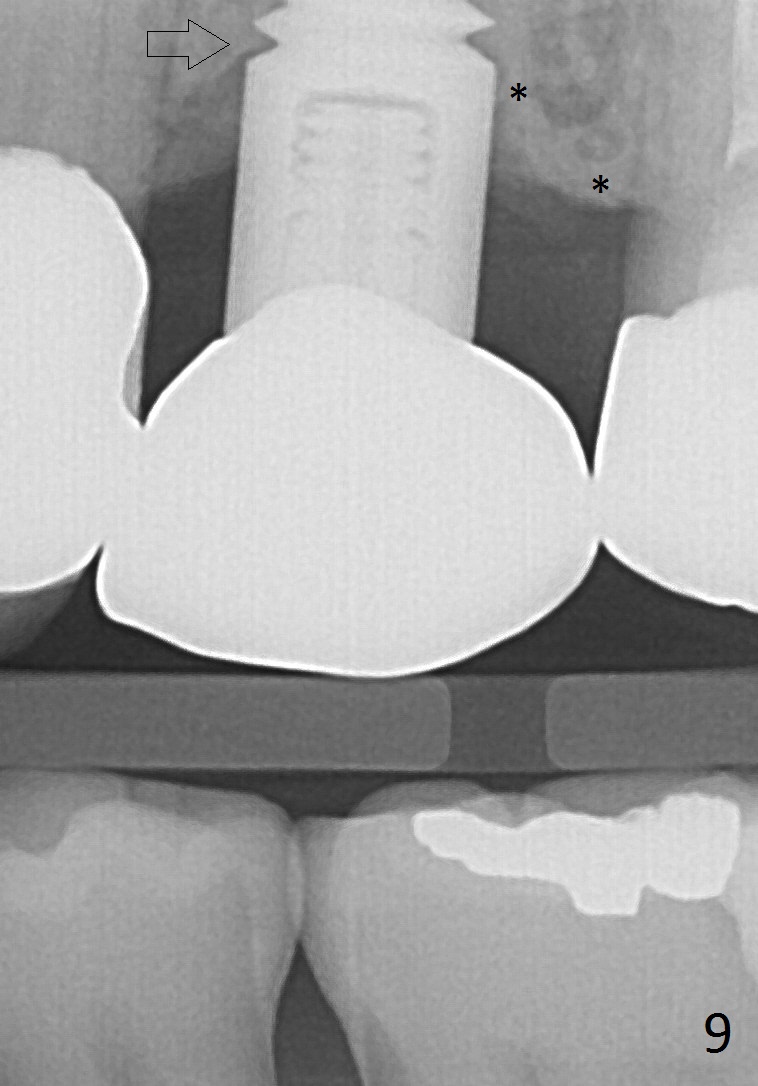

A 45-year-old lady is nervous about dental treatment. The missing tooth #13 was replaced by a 3-unit bridge. The latter is sectioned because the posterior abutment has caries. PA in Fig.1 is taken when root canal therapy and build up are finished. Fig.2 shows the wide edentulous area with a single-unit crown being tried in for #14. Osteotomy is initiated with the crown in place without cementation, since it is easy to determine the mesiodistal position (Fig.3 red lines). Without the crown in place, osteotomy tends to be distal. In this case, the osteotomy is later attempted to be moved distally with Lindamann bur and deepened to 14 mm from the gingival margin (Fig.4). A 2.5 mm reamer is being used at 50 RPM to increase osteotomy with difficulty. Drills have to used at high RPM instead (Fig.5 4x14 mm). A 4.5x14 mm tissue-level implant is placed with insertion torque >60 Ncm (Fig.6 I); a 4x3 mm abutment (A) is placed immediately for an immediate provisional. Fig.7 is taken 7 days postop to show the gingival recipient site formed by the provisional. The patient is so afraid of X-ray that the next one is taken 1.5 years post cementation (Fig.8). It appears that dense bone bundle forms between the crest and the 1st implant thread (adaptation functional change, arrowheads). The bone density continues to increase 2 years 8 months post cementation (Fig.9 *, 10); the bone has grown into the area between the 1st 2 threads (arrow).